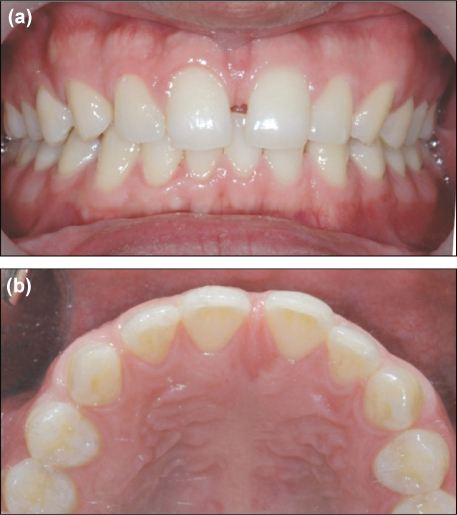

A 30-year-old male came to the department of conservative dentistry, Dankook university dental hospital, complaining about the space in the middle of front teeth. A clinical examination revealed 2 mm space between maxillary central incisors, with favorable gingival hygiene (

Figure 1). The patient didn't want orthodontic or prosthodontic considerations. The treatment plan to attain an esthetically favorable relation between the maxillary anterior teeth involved closing the diastema, nonsurgical gingival contouring of the interdental papilla using composite resin restorations.

Figure 1

Preoperative intraoral photographs.

(a) Frontal view, (b) Occlusal view.